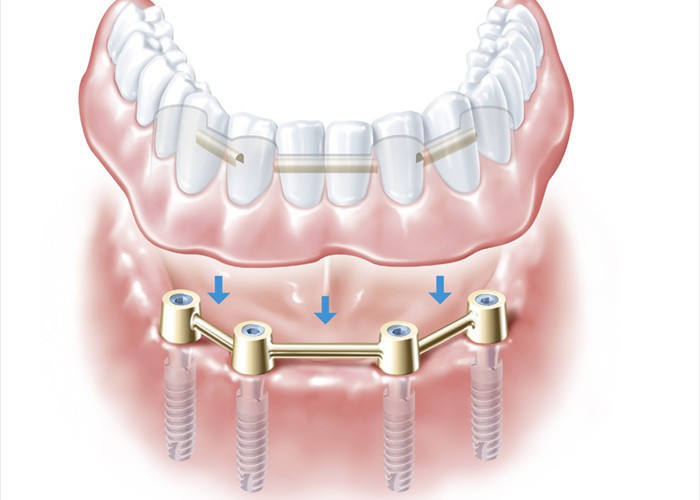

Wie der heraushembare Teil auf den festsitzenden passt. Wenn der Sitz einmal lockerer wird, kann er über die Stegreiter wieder fester eingestellt werden.

Wie der heraushembare Teil auf den festsitzenden passt. Wenn der Sitz einmal lockerer wird, kann er über die Stegreiter wieder fester eingestellt werden.